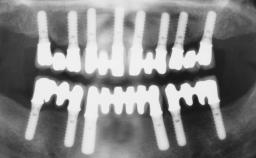

Immediate Loading of Two Implants in the Mandible and Final Restoration with a Bar-Supported RDP

A 56-year-old female patient was referred to the clinic because of retention problems with her mandibular denture. She had been completely edentulous for more than 33 years and wore her sixth set of complete conventional dentures, which had been delivered 5 years previously. An oral surgeon had performed a vestibuloplasty in the interforaminal region of the mandible with a piece of skin tissue 12 years earlier. The panoramic radiograph and lateral cephalometric radiograph exhibited the hypotrophy of the inferior alveolar process. The mandible was a Cawood class VI,and the height of the mandible in the interforaminal zone was 15 mm.

# of Implants 2

Type of Implants One-Piece

Modality 2 interforaminal implants